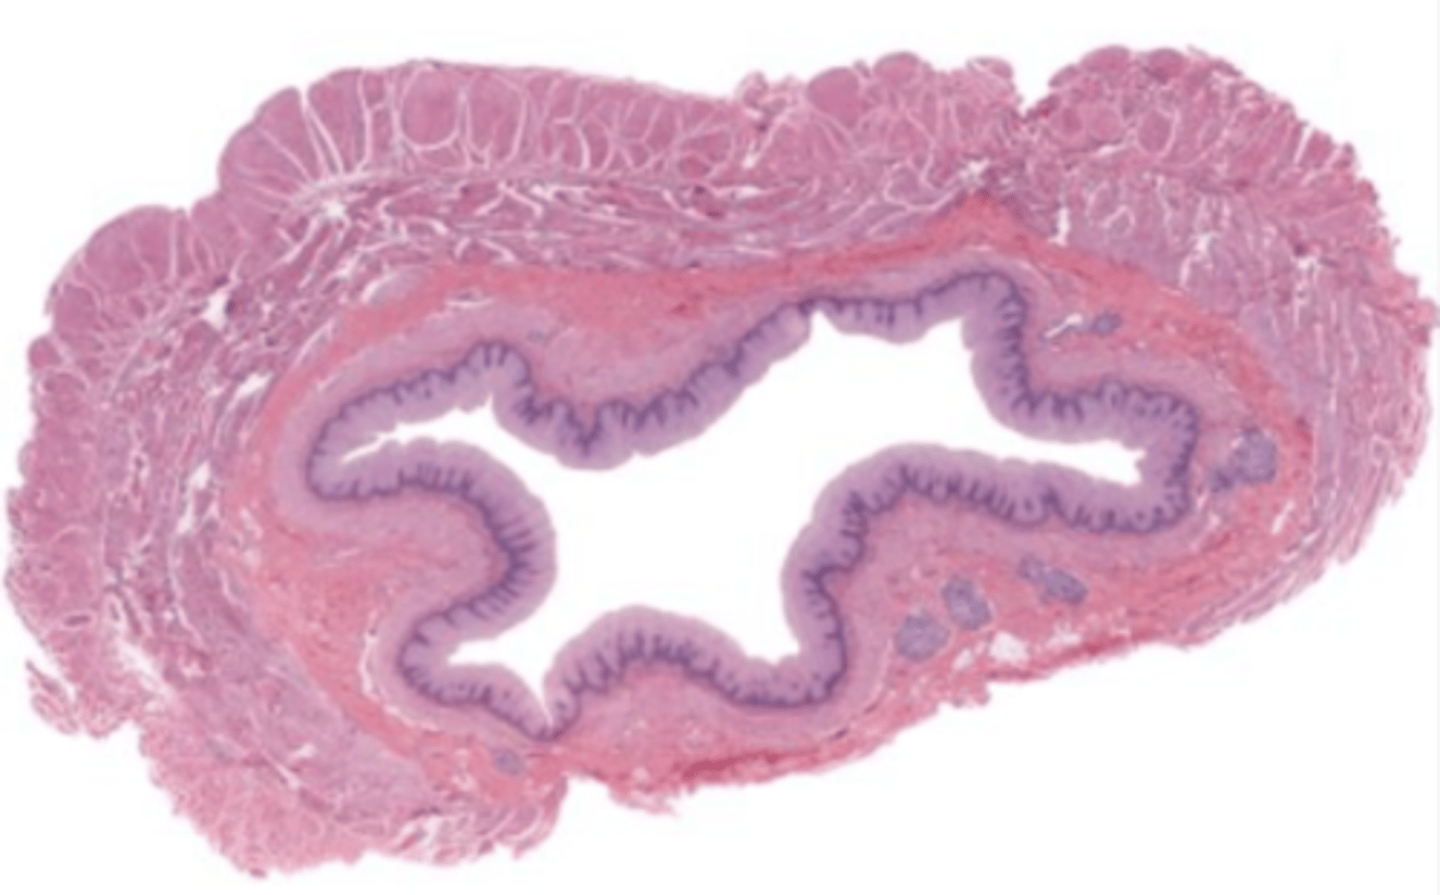

colon (histology)

simple columnar epithelium

what kind of epithelium lines the mucosa of the colon?

intestinal glands/crypts (colon)

lumen (colon)

mucosa (colon)

mucosal epithelium (colon)

lamina propria (colon)

muscularis mucosa (colon)

submucosa (colon)

contains glands and blood supply

muscularis externa (colon)

serosa/adventitia (colon)